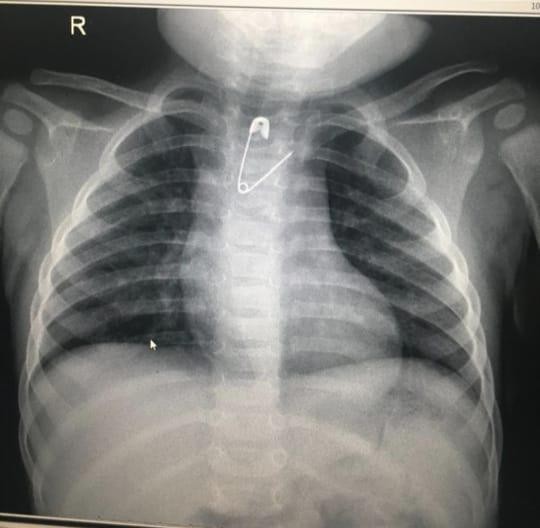

تمكَّن فريق طبي بمستشفى الولادة والأطفال عضو التجمع الصحي بمكة المكرمة من إنقاذ طفلة بعمر 8 شهور بإزالة مشبك مفتوح عن طريق المناظير دون إجراء إي تدخل جراحي.

وقاد العملية الدكتور علي الشمراني وطبيب التخدير د.أنس بركات، حيث أوضح د. الشمراني قائلاً : أن مثل هذه الحالات تعد نادرة وذلك لصغر عمر الطفلة وتعتبر هذه الطفلة الأولى التي يستخرج منها هذا الجسم الغريب (المشبك) على مستوى المنطقة بعمر لم يتجاوز 8 أشهر من الجزء العلوي بالمريء, كما نوه بالتعاون البناء بين الأقسام المختلفة ومنها الأشعة والتخدير في علاج المرضى.